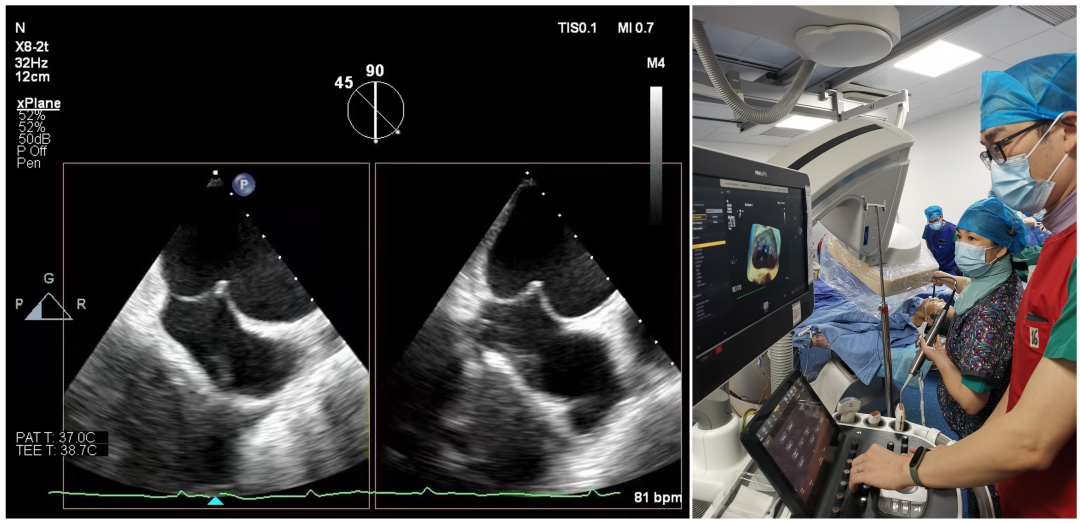

手术当天,江洪教授、陈静教授在经食道心脏超声(超声专家周青主任)实时指导下,按照标准流程精准穿刺房间隔,为手术的成功奠定基础。

食道彩超引导下房间隔穿刺